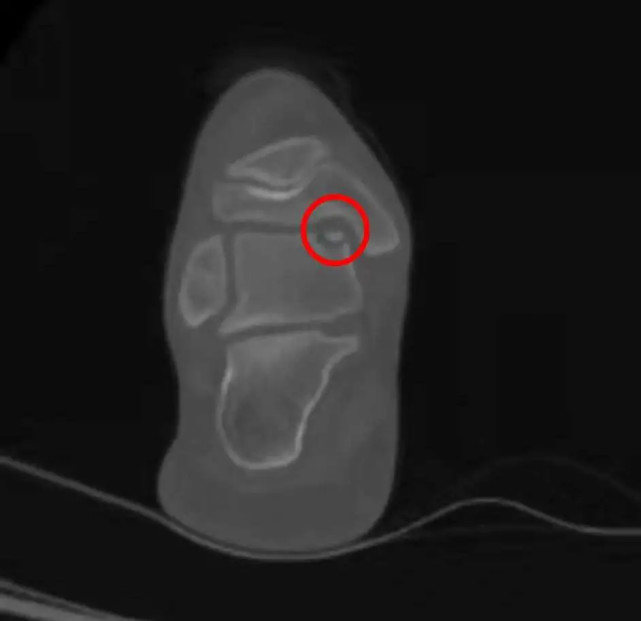

图一 a图ct显示距骨软骨损伤,b图核磁共振显示距骨软骨损伤影响到软骨下骨

答:距骨骨软骨损伤的临床表现无特异性,常由于外伤崴脚后通过拍片发现,也有出现踝关节疼痛后发现,X片和CT上软骨不显影但可显示病变范围,MRI不仅可以清晰显示软骨同时可判断周围韧带、软组织损伤情况,诊断准确率81-92%。